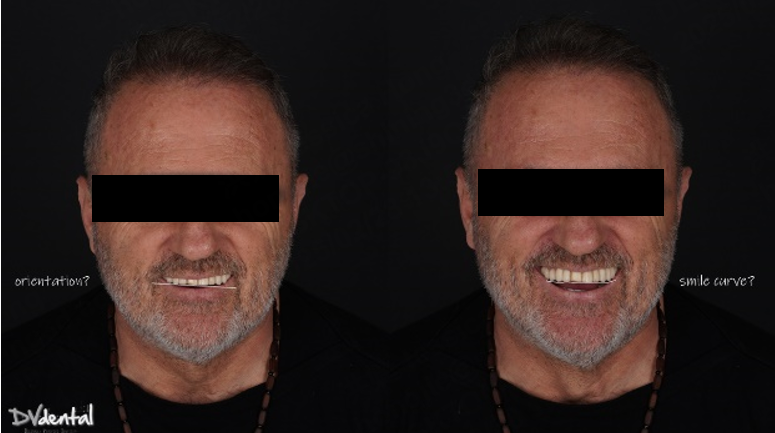

Additionally, due to the skewed smile line and unattractive appearance of the previous maxillary prosthesis, the patient expressed a desire for a more aesthetically pleasing design for the new restoration. To achieve this, we will use SHINING3D’s MetiSmile facial scanner to capture the patient’s facial data and use this data as a reference for smile design.

In aesthetic design, facial data can assist technicians in analyzing the patient’s facial symmetry, smile line, and the proportion of teeth to facial features, ensuring that the prosthesis harmonizes with the patient’s facial characteristics. Therefore, the application of facial scanners is crucial. The MetiSmile facial scanner from Shining 3D can capture the patient’s 3D facial data with high precision, including facial contours, lip morphology, nasolabial folds, and chin position. These data provide essential references for the aesthetic design of the prosthesis. Since both MetiSmile and Aoralscan Elite belong to the Shining 3D platform, the intraoral scan data and facial scan data can be directly matched during the facial scanning process.